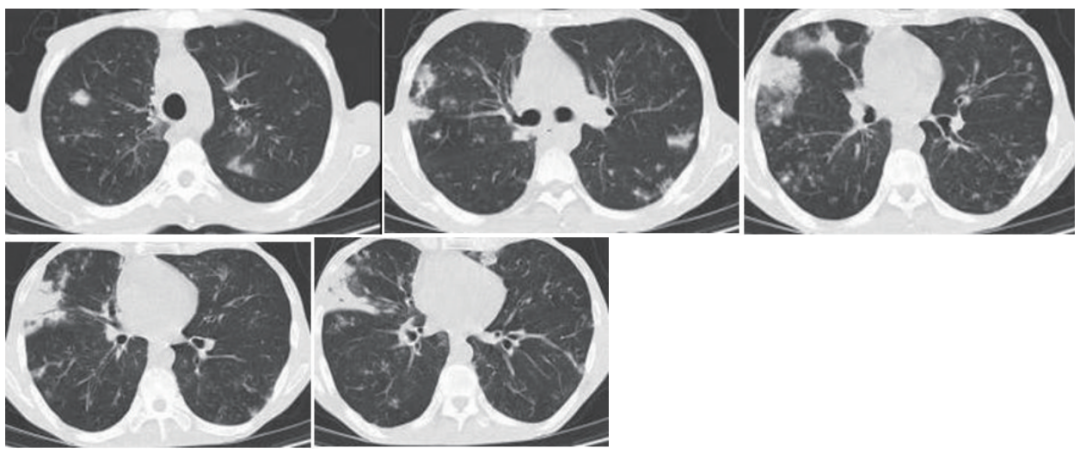

10余天前患者再次出现痰量增多,为黄灰色痰,吸氧状态(2~4 L/min)下仍感气短,日常生活不能自理,躯干、四肢及头皮均可见水泡样皮疹及红色丘疹,同时伴瘙痒。就诊于我院急诊,胸部CT示双肺支气管扩张,双肺多发斑片状渗出影,较前进展(图3);血气分析示Ⅰ型呼吸衰竭,为进一步诊治以“支气管扩张症伴感染”收入呼吸科。患者自发病以来,精神、食欲差,睡眠差,大便不规律(便秘、腹泻交替),小便不畅(尿潴留、尿失禁交替),体重近半年下降8 kg。

图3 胸部CT(2024年9月)

呼吸科 回顾患者的病史及影像学资料,支气管扩张症在半年内出现,进展速度高于经典的感染后支气管扩张症,且目前亦不支持自身免疫性疾病、遗传性疾病等继发的支气管扩张症,胸部CT除了支气管扩张外,可见马赛克征、树芽征,应考虑闭塞性细支气管炎。文献显示,闭塞性细支气管炎常见于肺移植术后,此外可发生于30%的副肿瘤性天疱疮患者。

图6 胸部CT(治疗后1周)